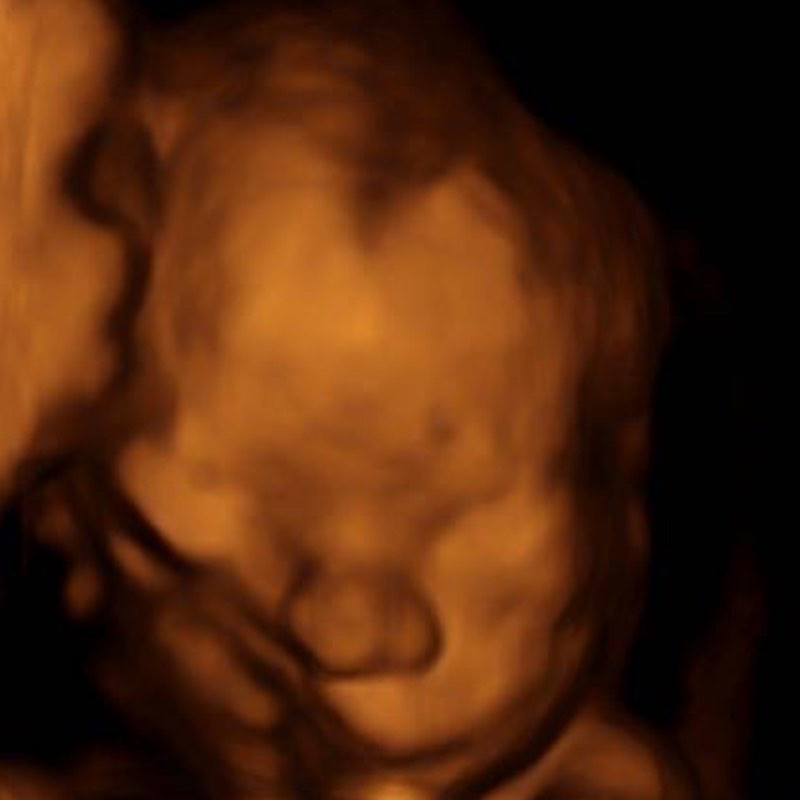

My business is a mobile ultrasound company. I come to your home, bring everything I need and do your Ultrasound while you lay on your couch surrounded by friends and family. I have had so much fun getting to know my families and doing all the fun parts of ultrasound. I do early pregnancy, gender reveals, baby showers, 2D and 3D/4D. Getting started wasn’t easy, I built my website, I got an equipment loan, I got some quotes, purchased my equipment and started advertising my services with social media.